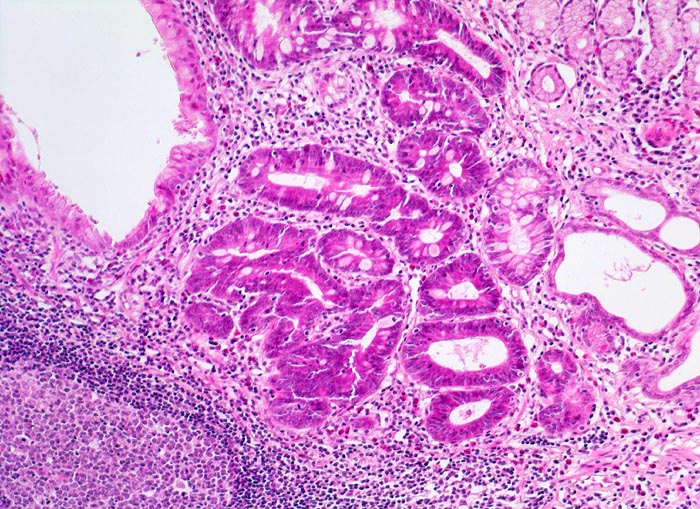

• Vier Magenschleimhautbiopsien (Oberstes: Antrum/Corpusübergang mit intestinaler Metaplasie, zweitoberstes und unterstes: Antrumschleimhaut mit intestinaler Metaplasie, zweitunterstes: Corpusschleimhaut mit intramukosalem Lymphfollikel ohne Metaplasie).

• Schwere chronische (dichtes lymphoplasmazelluläres Entzündungsinfiltrat in der Lamina propria), stark aktive (neutrophile Granulozyten in der Lamina propria und im Epithel mit Ausbildung von Mikroabszessen) Gastritis.

• Typisch für Helicobactergastritis: intramukosale Lymphfollikel

Das Unterrichtspräparat zeigt eine Helicobacter-Gastritis mit intestinaler Metaplasie. Histologisch ist die Typ B Gastritis charakterisiert durch eine chronische (Plasmazellen und Lymphozyten) und aktive (neutrophile Granulozyten) Entzündung. Das Ausmass der chronischen Entzündung und die Entzündungsaktivität werden gemäss Sydney Klassifikation in drei Schweregrade unterteilt (z.B. mässiggradige chronische, stark aktive Gastritis). Fakultativ können Lymphfollikel, eine intestinale Metaplasie mit/ohne Dysplasie und/oder Drüsenatrophie hinzukommen. Die Erreger (Helicobacter pylori) kolonisieren den protektiven Schleimfilm auf der Magenmukosa (> 3330) (> 9968) und sind dort mittels Spezialfärbung (Giemsa C) mikroskopisch nachweisbar. Unmittelbar im Bereich der intestinalen Metaplasie sind aufgrund des veränderten Milieus meist keine Bakterien nachweisbar. Unter Einnahme von Säurehemmern oder Antibiotika verringert sich die Sensitivität des Bakteriennachweises in der Biopsie aufgrund der schnellen Reduktion der Bakterienanzahl ebenfalls. Nach erfolgreicher Eradikation verschwindet in der Regel die aktive Entzündung innert Wochen. Chronische Entzündung und Lymphfollikel bleiben jedoch länger nachweisbar und geben einen Hinweis auf eine abgelaufene Helicobactergastritis.